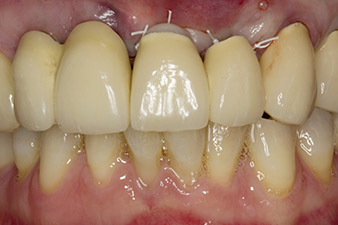

Tooth 23 displayed a horizontal-coronal fracture and was restored with a post and core build-up for the temporary restoration. The plan was to place a zirconium oxide bridge on the existing implants at positions 12 and 11 and to place two new implants at positions 22 and 23.

In this case study, the situation was resolved with an implant at position 22 in the first procedure and an additional one at the position of the extracted tooth 23 later in the course of the treatment. The second implant was inserted following successful osseointegration of implant 22. The revised bridge was reinserted until implant 23 healed in place and the shaping for the permanent restoration was complete. The advantages of this gradual approach include the implants’ being able to accept loads more resiliently and mature hard and soft tissues (5).